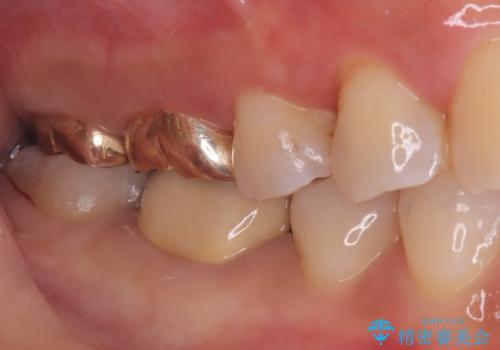

クリーニングにいらした患者さんで、右下7番目の歯の奥側の面や手前の歯との間にう蝕があり、噛む面にも蝕処置によるレジン材料が詰まっていたことから、う蝕も古い材料も全て除去しセラミックインレーでのやり替えとなりました。

右下7近遠心にカリエスを認め、咬合面のCR修復も劣化していたので、カリエスと古い材料を全て除去し新しくCR裏層した後、セラミックインレーをセットしています。セット時はラバーダム防湿を行っています。